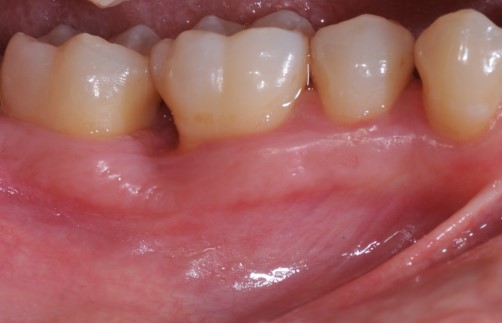

02/22 - Pre-surgical clinical situation, lingual view.

Deep intrabony defects treated using Straumann® Emdogain® - Dr. M. Stefanini